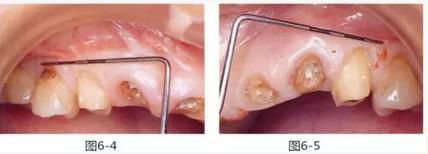

圖6-4,5

左上2,3和右上1,3存在齦下齲壞,但牙齒周圍有充足的角化齦。左上4和右上4頰側(cè)的角化齦較少。